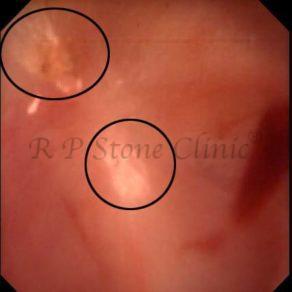

Kidney stone is a solid mass of CRYSTALS. It is the process of crystallization which initiates the formation of kidney stones. This happens in nephrons or units of kidney. Once a small crystal is formed, it can both grow & unite with other crystals leading to the formation of small concretion which eventually forms a stone. Once these large crystals detach from the collecting ducts, the process of stone formation starts in the renal collecting system. A recurrent kidney stone former is advised to know a little bit about something known as Randall’s plaque. Alexander Randall discovered plaques on the renal papillae eight decades back based on examination of 1154 pairs of autopsied Kidneys. He described these renal papillary lesions as cream colored or milk patch areas composed of calcium phosphate & calcium carbonate. These plaques could act as NIDUS for formation of KIDNEY STONE. Calcium Oxalate stone can form on this nidus & then detaches from this plaque to become a free floating stone in the collecting system of kidney

These images are taken as snap shots from the video recording of RIRS Surgery done at our hospital. These are Randall’s Plaques seen with Digital FLEX XC & Digital FLEX XC S. The cream or whitish patches are seen on the tips of RENAL PAPILLAE as seen in images below.

Randall’s Plaques may lead to the formation of Stones.

Those kidney stone patients who have Randall’s Plaques in their kidneys are more likely to form stones again (Recurrent Stones).